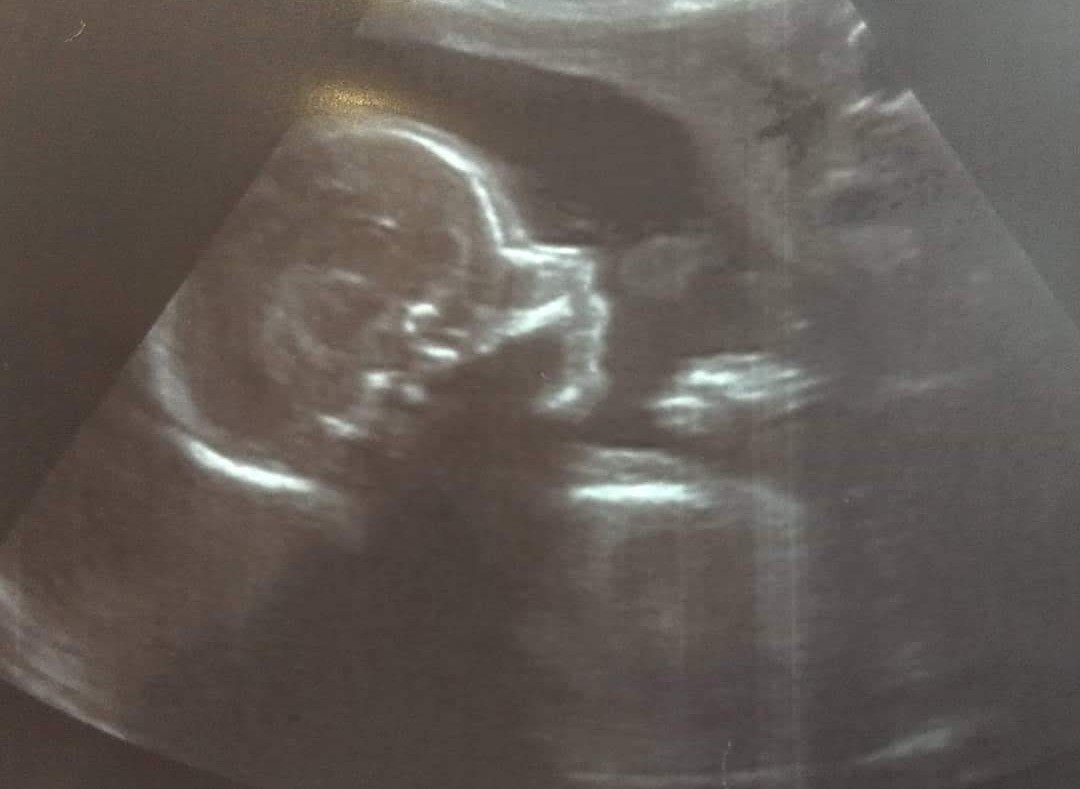

And this is bump (human hopefully, but type TBC). ETA May.